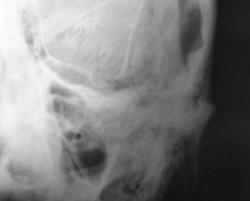

Пациент в ургентном порядке, после ДТП был доставлен в ЦРБ в ночное время. Был вызван "ургентный лаборант" для рентгенографии черепа. Пациент без сознания. С учетом состояния пациента рентгенография произведена в нестандартных проекциях - "задняя прямая".

Линейный перелом костей крыши черепа, возможно с переходом на основание. Вот только не понятно есть или нет импрессионный перелом височной кости, а ещё больше похоже на наличие пневмоцефалии.

А что скажите по поводу пирамидки и орбиты справа?

Контуры пирамиды чёткие, а вот латеральная стенка орбиты возможно сломана. Он был отправлен в ОКБ?

Линейный перелом с переходом на основание - дно средней черепной ямки. Сейчас вопрос о пирамидке и орбите не принципиальный. Главный вопрос нет ли внутричерпной гематомы. Если больной выйдет из тяжелого состояние, и встанут экспертные вопросы можно сделать Стенверс при потере слуха, Майер при кровотечении из уха. Насчет стенки орбиты - наличие перелома сомнительно, явно не видно. Также можно доснять при улучшении состояния. Судя по всему это молодой человек. Сколько лет?

Вижу только линию перелома височной и теменной костей, высока вероятность перехода на основание, остальное - домыслы и сомнения.